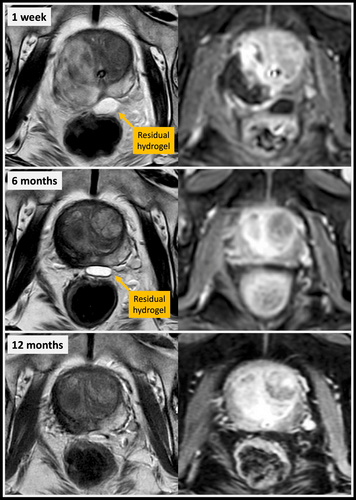

Scientific Library Koelis To assess the accuracy of koelis fusion biopsy for the detection of prostate cancer and clinically significant prostate new updates straight to your inbox. yes, i agree with the privacy policy and terms and conditions. Our study reported the outcome of a multi modality focal therapy (ft) cohort for localized primary prostate cancer. cryotherapy for posterior lesions of the prostate: the hydrogel t cryotherapy as one of the most established focal therapy tools has demonstrated satisfactory oncological and fu.